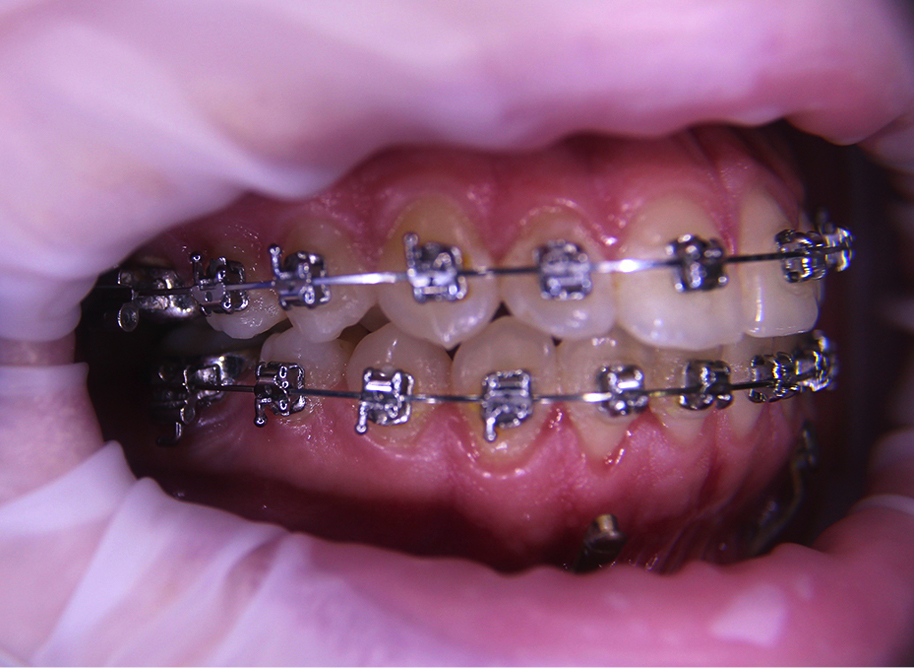

Streszczenie: Wady klasy III są uwarunkowane niedorozwojem szczęki lub nadmiernym wzrostem żuchwy, a często połączeniem obu tych nieprawidłowości. Należą one do nieprawidłowości zgryzowych i/lub szkieletowych. Możliwości leczenia niedorozwoju szczęki u pacjentów rosnących obejmują: zastosowanie maski twarzowej Delaire’a, zastosowanie maski w powiązaniu z RME, dystrakcję szczęki – po osteotomii w linii złamania Le Fort I, zastosowanie aparatu RED (ang. Rigid External Distractor) oraz zastosowanie zakotwienia szkieletowego. Celem artykułu jest przedstawienie przypadku skojarzonego chirurgiczno-ortodontycznego leczenia, przy użyciu minipłytek Bollarda u pacjenta rosnącego, z nienasiloną wadą szkieletową klasy III, ze zgryzem krzyżowym całkowitym lewostronnym i stłoczeniami w górnym oraz dolnym łuku zębowym. Materiał i metoda: 12-letnia pacjentka zgłosiła się do Poradni Ortodontycznej w Olsztynie z powodu wysuniętej żuchwy. Badaniami zewnątrzustnym, wewnątrzustnym i teleradiogramem bocznym głowy potwierdzono rozpoznanie: wada klasy III na tle niedorozwoju szczęki, wraz ze zgryzem krzyżowym całkowitym lewostronnym i ze stłoczeniami. Pacjentkę poddano dwuetapowemu chirurgiczno-ortodontycznemu leczeniu. W I fazie trwającej ok. roku [...]